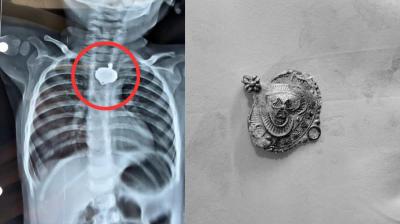

भारत ही नहीं विदेशों तक ‘चूहा कांड’ के चर्चे, वर्ल्ड मीडिया में एमवाय की थू-थू

14 Sep, 2025 01:00 PM IST | RASHTRIYAJANADESH.COM

Indore MY Hospital: अफसरों, डॉक्टरों और कर्मचारियों की लापरवाही से एमवाय अस्पताल में दो नवजातों को चूहों के कुतरने और फिर उनकी मौत होने का मामला विदेशों में भी चर्चा...